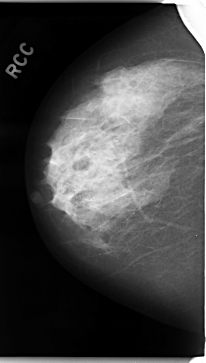

C_0017_1.RIGHT_CC

RIGHT_CC LINES 4712 PIXELS_PER_LINE 2672 BITS_PER_PIXEL 12 RESOLUTION 50 NON_OVERLAY